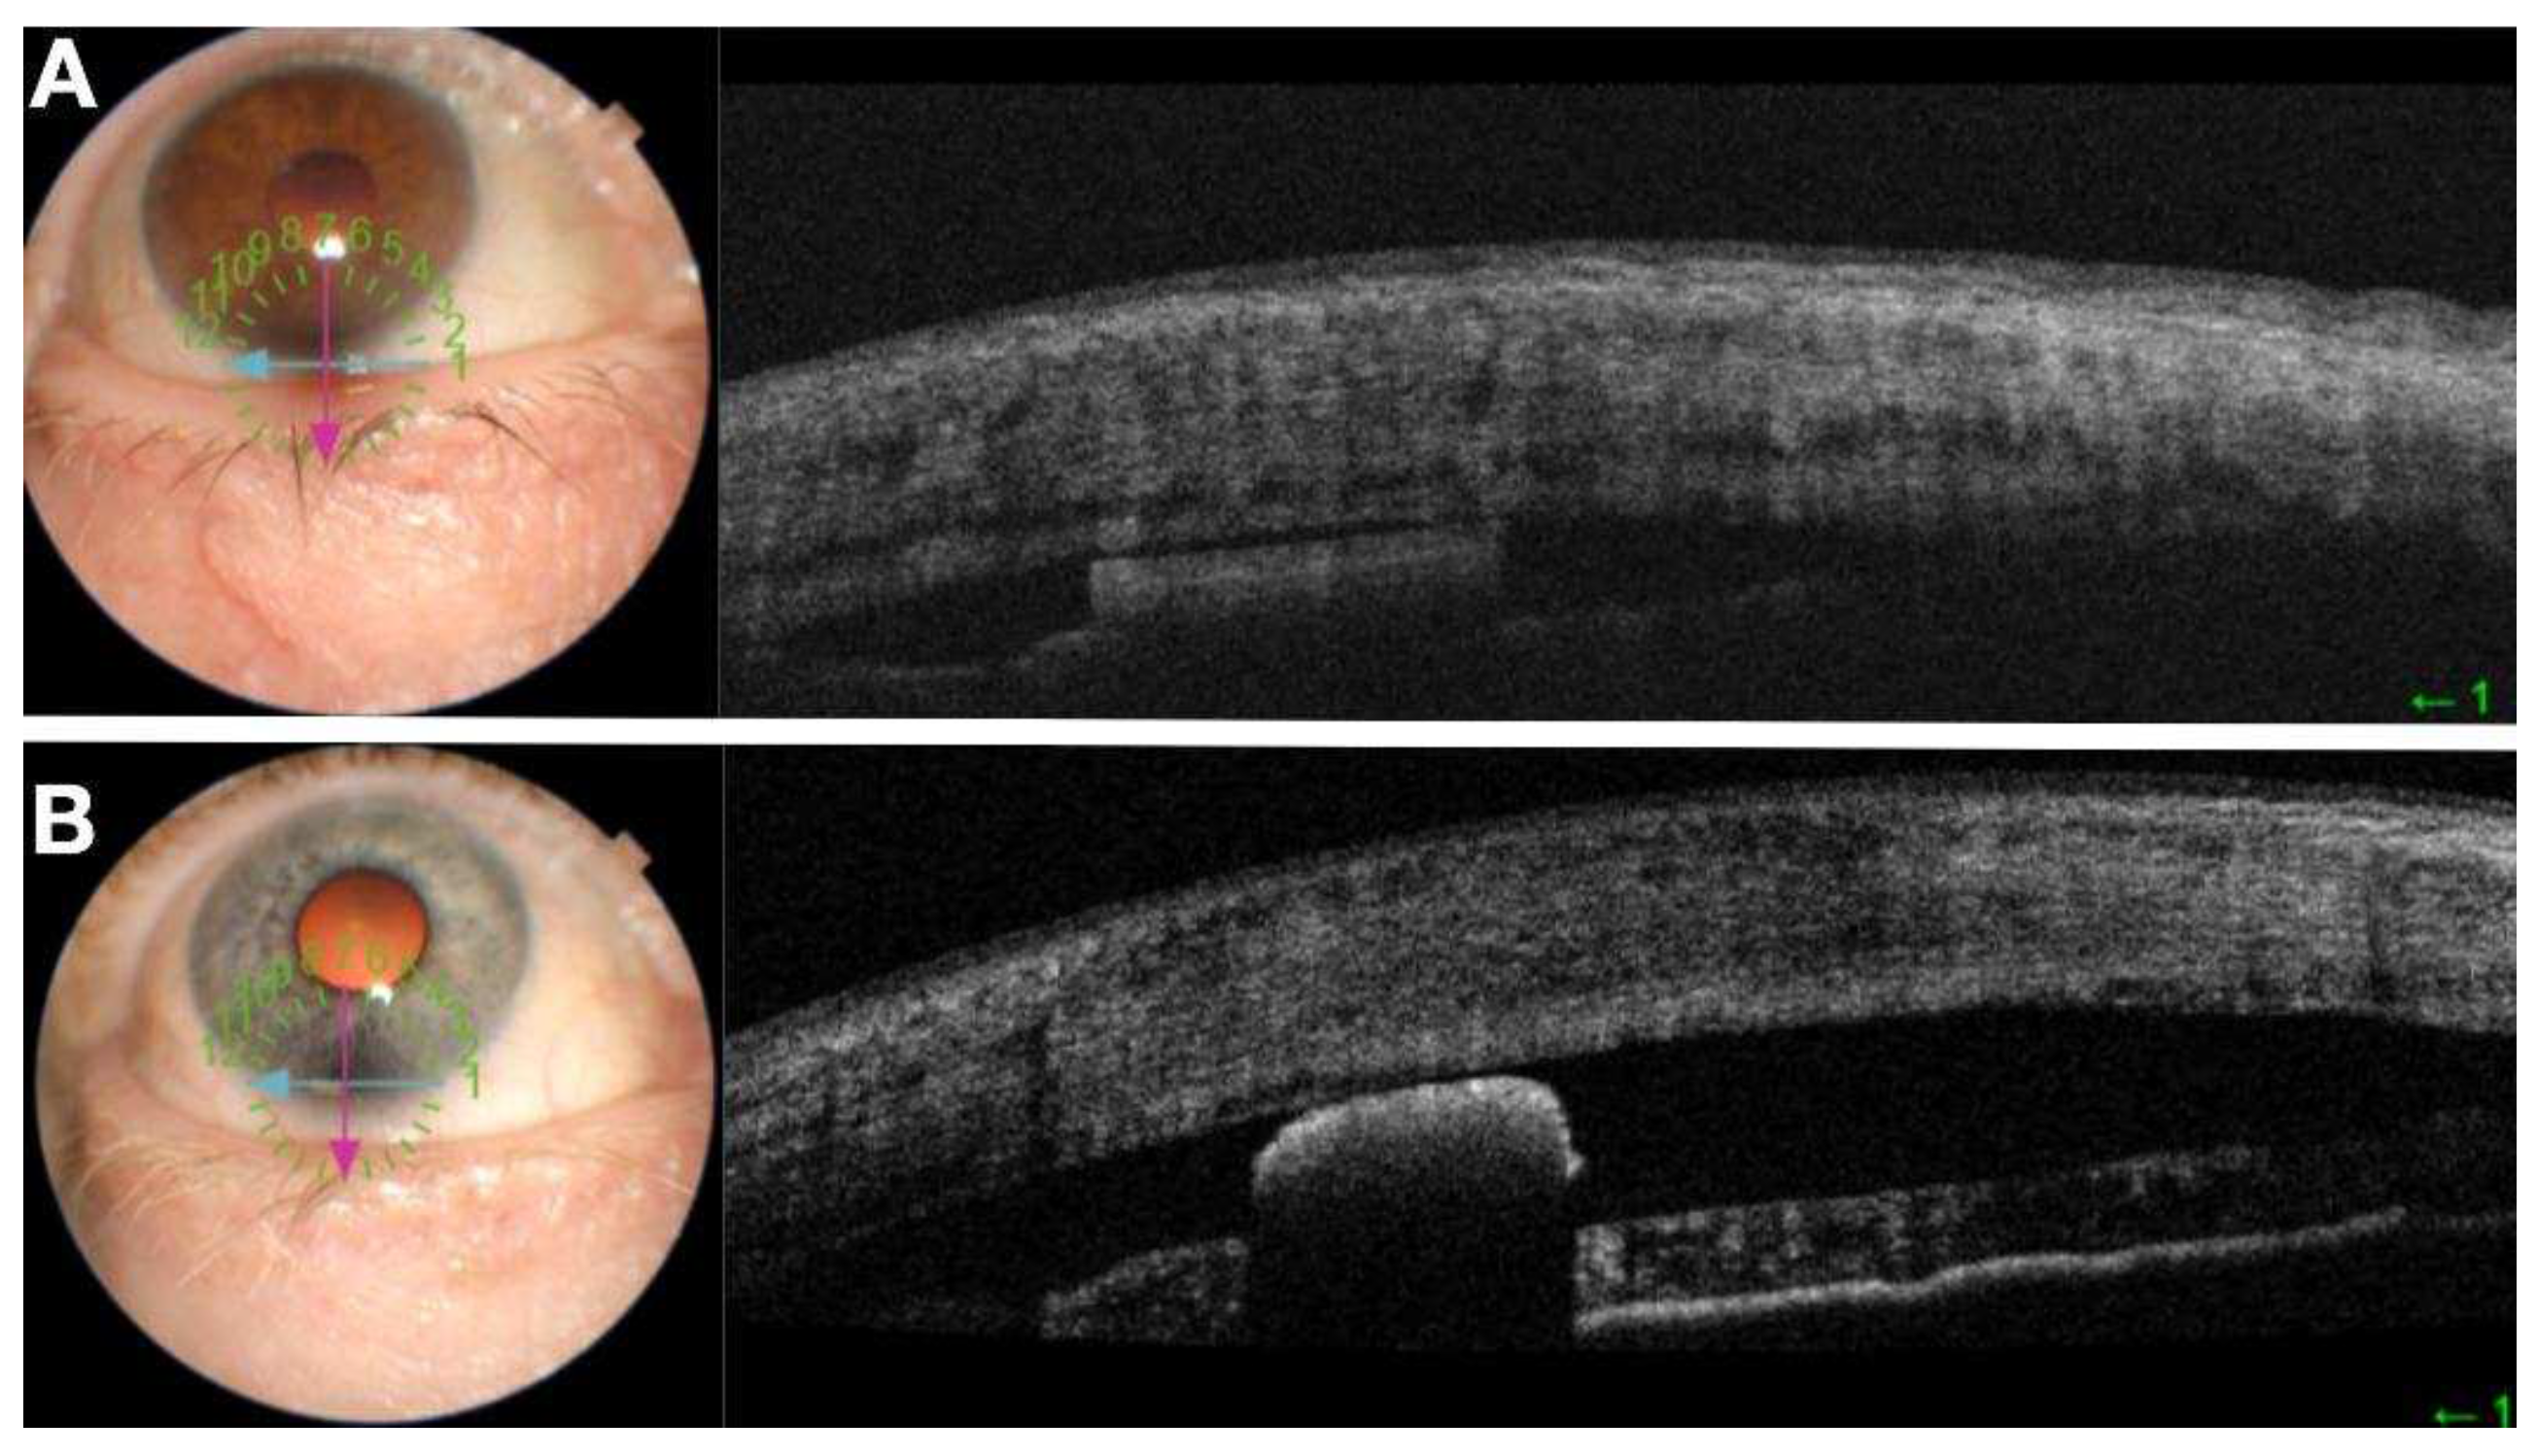

Figure 3. Anterior Segment OCT of intracameral DURYSTA implantation (a) followed by one month post implantation of a non-mobile implant (b). Note implant is not round.